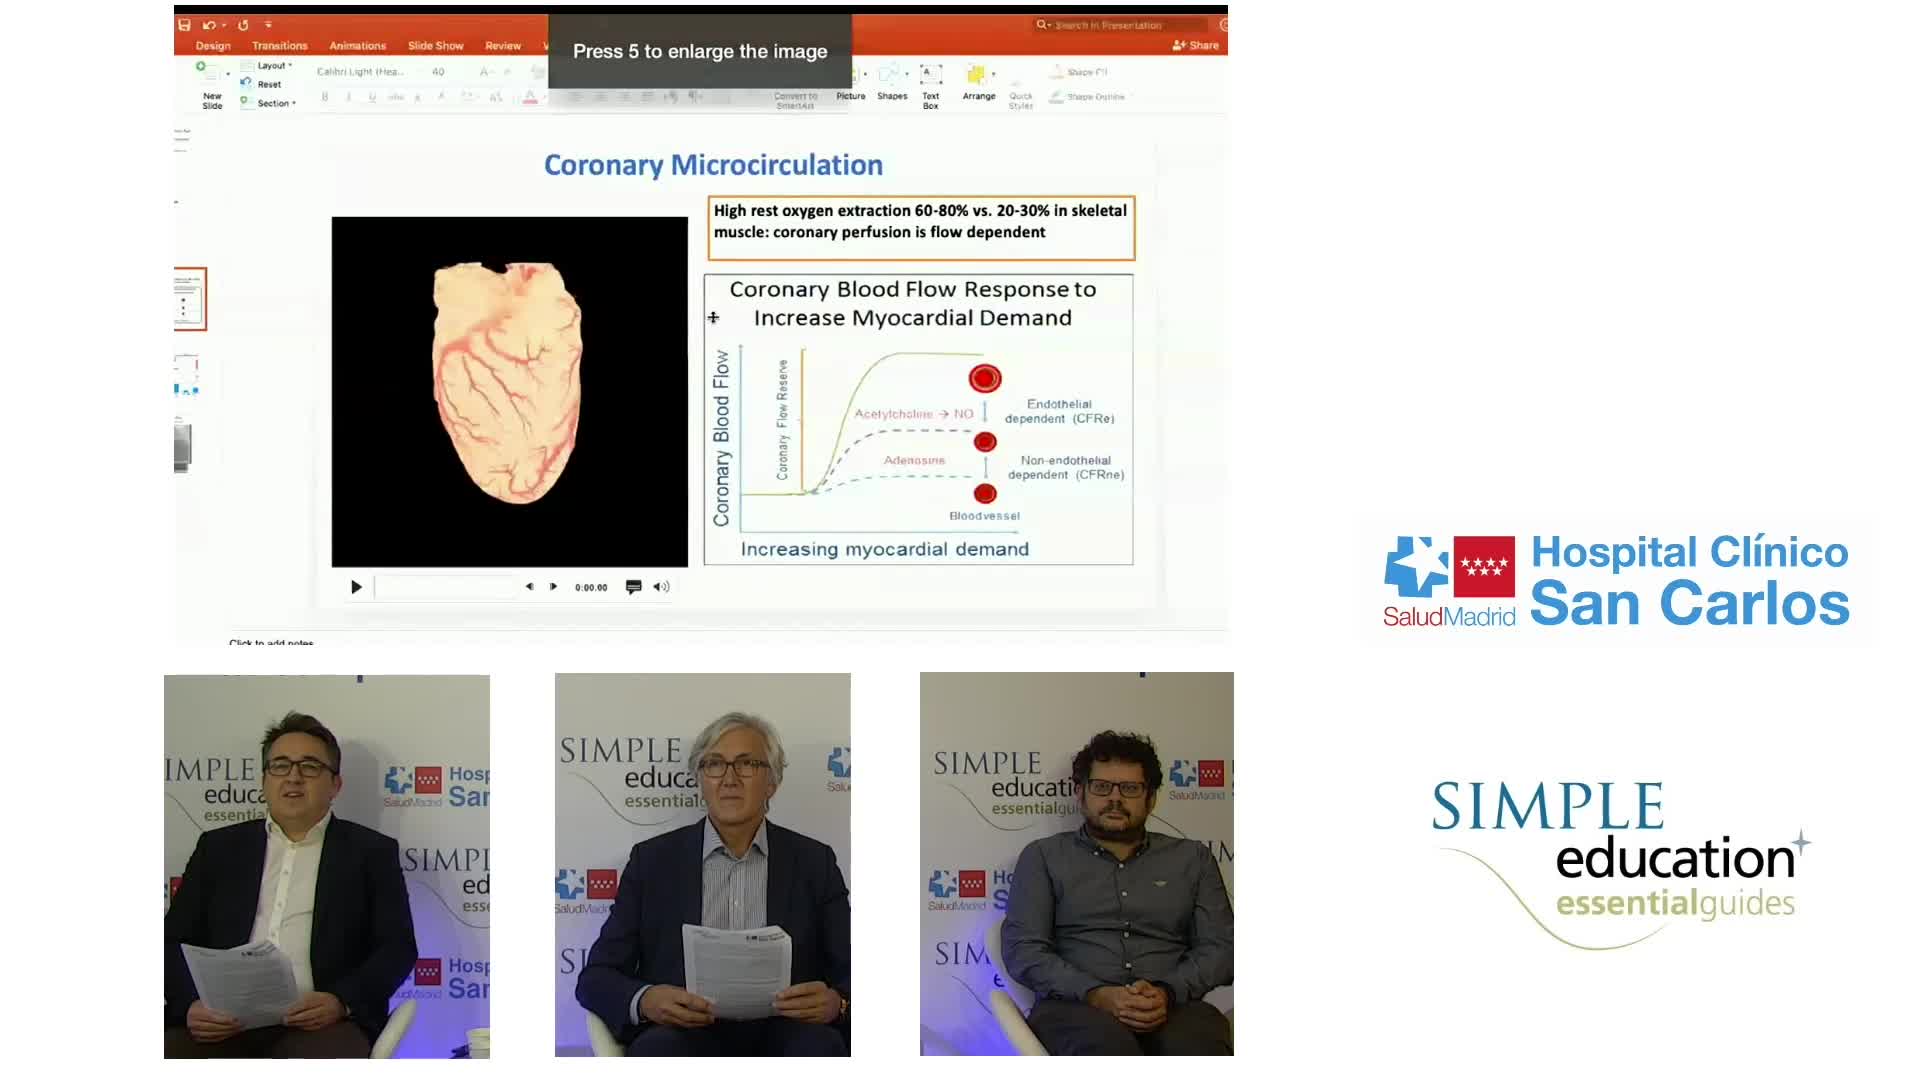

Why is the physiology negative? Integration of the coronary microcirculation to decision-making

Understanding mechanisms of regulation of resting and hyperaemic blood flow, across single and serial stenoses

ABC for using Coronary Physiology in Aortic Stenosis, Primary Percutaneous Coronary Intervention (PPCI)/ACS, Muscle Bridges and Atrial Fibrillation - Dr Ricardo Petraco